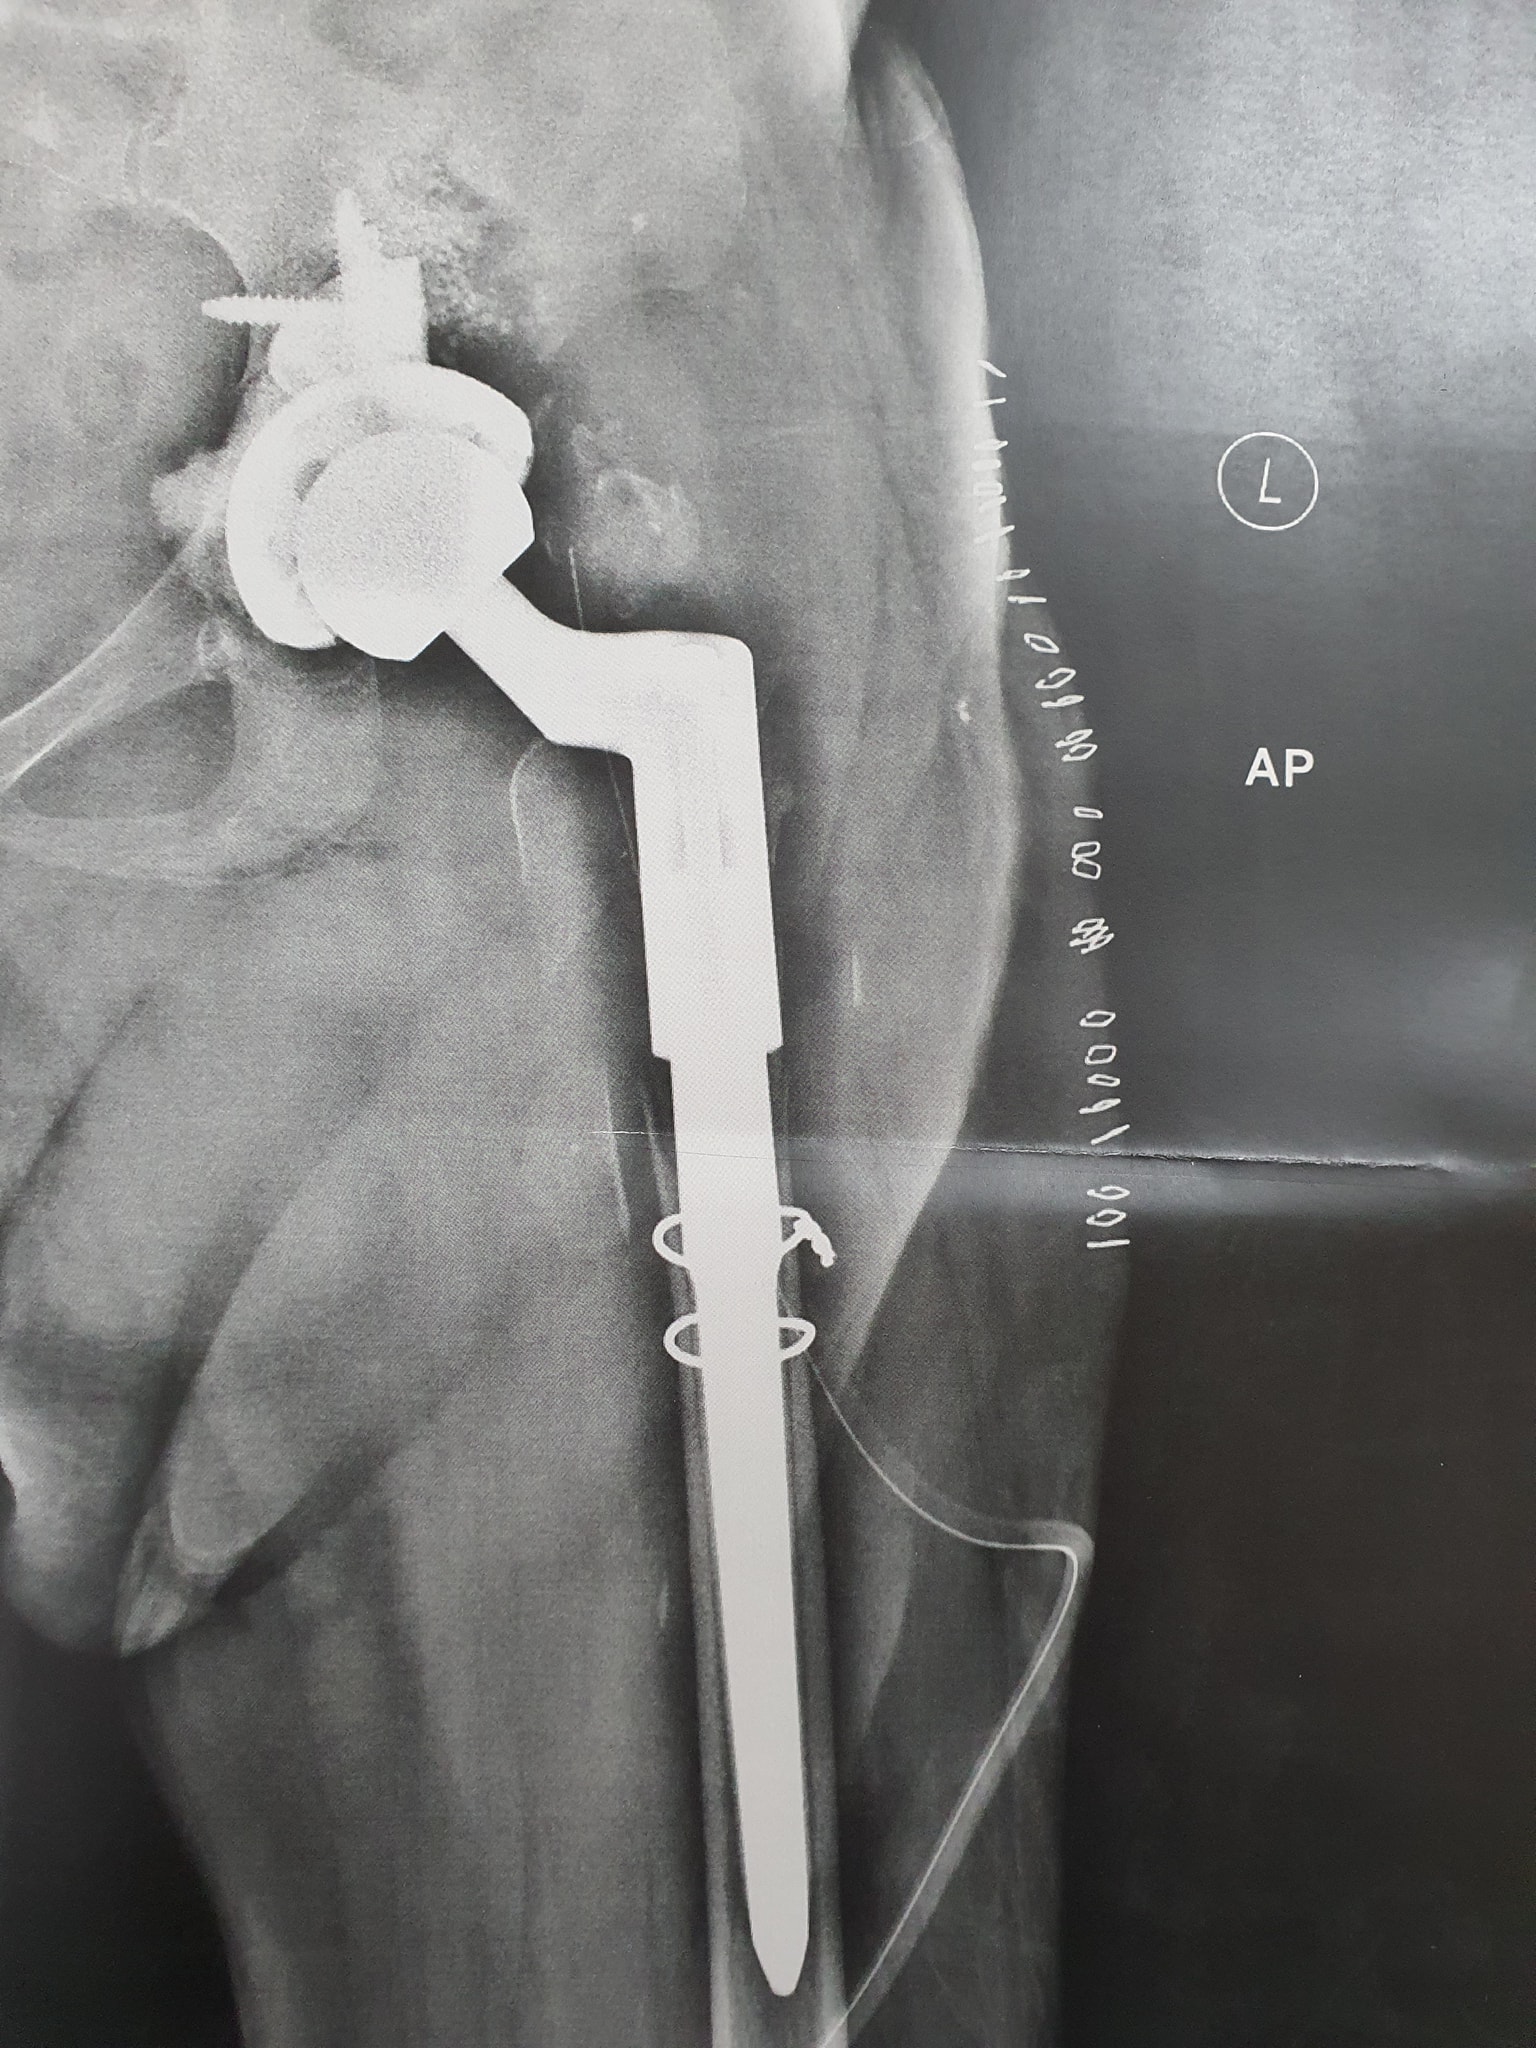

زراعة المفاصل الصناعية ورك و